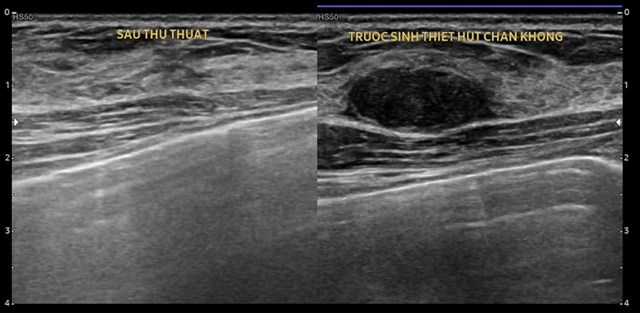

Hút chân không u vú: Giải pháp hiệu quả trong chẩn đoán và điều trị

Trong lĩnh vực chẩn đoán và điều trị bệnh lý tuyến vú, phương pháp hút chân không u vú là một kỹ thuật tiên tiến, mang lại nhiều lợi ích vượt...